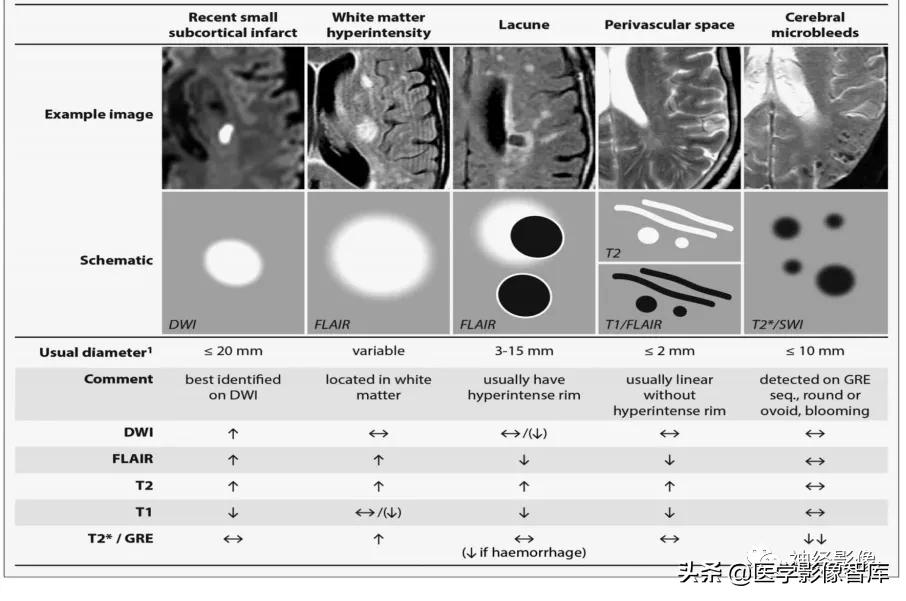

腔隙性梗死的长期动态变化

参考文献:Update on cerebral small vessel disease: a dynamic whole-brain disease Stroke Vasc Neurol. 2016 Oct 25;1(3):83-92.